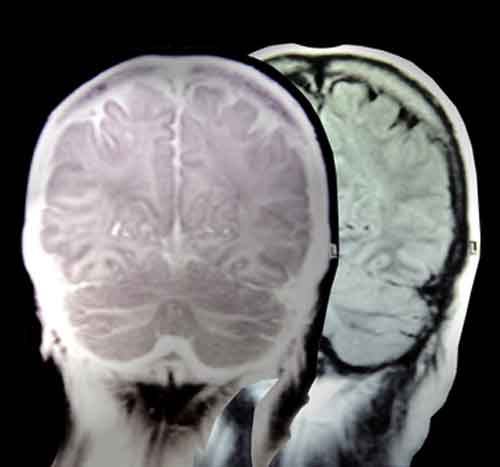

Molti pazienti con una diagnosi di epilessia potrebbero essere semplicemente stressati, come rivela un nuovo studio della Johns Hopkins University School of Medicine negli Stati Uniti.

Negli ultimi mesi, la percentuale e’ salita fino alla meta’. Hanno movimenti incontrollati e convulsioni che assomigliano a quelle dovute all’epilessia”, ha spiegato Jason Brandt, psichiatra a capo dello studio pubblicato sulla rivista Seizure. “Tuttavia non sono il risultato di scariche elettriche cerebrali anormali come nella vera epilessia – ha aggiunto – ma comportamenti causati dallo stress che ne replicano i sintomi”. Chi soffre di PNES non si trova necessariamente piu’ spesso in situazioni stressanti, ma e’ meno capace di sopportarle. “Questo causa false diagnosi e prescrizioni di farmaci e trattamenti inutili – ha concluso Brandt – vivere sapendo di avere l’epilessia comporta pesanti conseguenze sociali e psicologiche, e un sacco di pazienti starebbero meglio se sapessero che non hanno un problema neurologico ma sono solo stressati”.